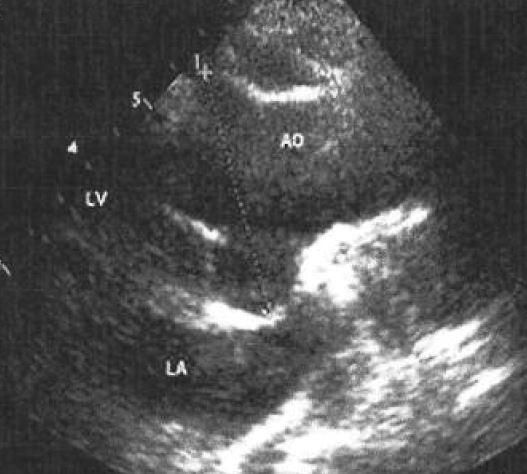

Aşağıdaki resimleri inceleyiniz. İlk resimde hastalığı olmayan bir kişinin ekosu yapılmıştır. AO ile yazan yer hastanın AORT DAMARI dır. 2. resimde ise Marfan hastalığı olan bir kişinin kalp ekokardiyografisi. Dikkat edilirse AO yazan aort damarı genişlemiş ve kapak düzenliliği bozulmuştur. İşte bu yüzden Marfan hastalığında 6 ayda bir eko tetkiki ile takibi gereklidir.